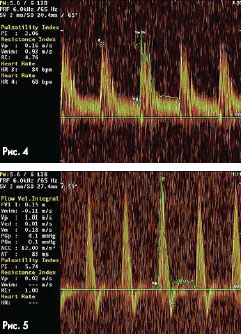

Характеристики кровотока

В режиме цветного (ЦДК) и импульсного доплеровского картрирования определяют параметры кровотока при помощи специального сосудистого программного обеспечения.

Как показано на рис. 3, датчик устанавливают по направлению к кровотоку под углом не более 600 к предполагаемой оси сосуда и добиваются получения высокого чистого акустического сигнала без шумовых помех с четким графическим изображением на экране монитора, после чего включают запись доплерограммы.

Регистрация доплеровских сигналов кровотока в виде аналоговых кривых скорости (доплерограмма) дает возможность провести анализ скорости кровотока в исследуемых сосудах с последующим расчетом по интерпретирующей программе.

Индексы периферического сопротивления, используемые для оценки периферического сопротивления сосудов, определяются по формулам:

RI=(Vmaxs-Vendd) / Vmaxs

PI=(Vmax-Vmin) / Vmean

Индекс резистентности (RI) определяется как отношение разности максимальной систолической скорости кровотока Vmaxs и конечной диастолической скорости кровотока Vendd к максимальной систолической скорости. Индекс пульсации (PI) определяется как отношение разности максимальной скорости кровотока Vmax и минимальной скорости кровотока Vmin к средней скорости Vmean в течение сердечного цикла. Средняя скорость Vmean - это усредненная по времени за сердечный цикл максимальная скорость потока.

PI зависит от всех скоростей кровотока, что дает ему преимущества с точки зрения информативности.

На рис. 4 и 5 продемонстрировано ручное построение огибающего доплеровского спектра с последующим расчетом по интерпретирующей программе.